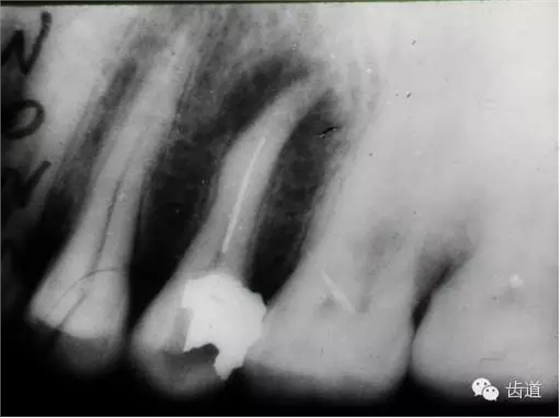

(3)髓室底穿孔:處理方法同上。同時(shí)找到根管口,按常規(guī)進(jìn)行根管預(yù)備和充填。如穿孔范圍太大易導(dǎo)致根分歧病變,予后欠佳??尚懈芡饪啤?/span> (4)根管壁形成臺(tái)階:先換小號(hào)銼去除臺(tái)階,再順序擴(kuò)挫。如根管壁穿孔,找到主根管進(jìn)行預(yù)備后,主根管及側(cè)穿道同時(shí)充填。在根尖1/3或根尖彎曲處側(cè)穿,根充后,配合根尖手術(shù)——根切+倒充填。 (三)髓腔壁穿孔的預(yù)防 1.掌握每個(gè)牙齒的髓腔解剖形態(tài)及其在牙齒表面的投影范圍。 2.術(shù)前拍X線片。 3.進(jìn)行規(guī)范化操作,隨時(shí)與X線片核對(duì)器械進(jìn)入方向及進(jìn)入深度。 器械折斷在根管內(nèi),阻塞根管,妨礙治療操作。如不能取出,使根管治療不能繼續(xù)進(jìn)行,不得不輔以根尖手術(shù)。 左上7近中頰根器械折斷 右上6腭根器械折斷 1.器械本身的原因 材料質(zhì)量欠佳,受力后易折斷。 器械反復(fù)使用,產(chǎn)生折痕,用力后也易折斷。 消毒方法不當(dāng),消毒液中未放防銹劑,器械銹蝕易折。 2.術(shù)者器械使用不當(dāng) 遇有阻力,仍強(qiáng)行進(jìn)入,用力過(guò)大過(guò)猛,超過(guò)了器械所能承受的程度 未按操作要求使用器械(跳號(hào)) 器械在細(xì)窄根管內(nèi)被卡住后,仍勉強(qiáng)旋轉(zhuǎn)器械柄 折斷于根管內(nèi)的器械要盡量取出,若無(wú)法取出經(jīng)常規(guī)充填后,成功率不受明顯影響。 1.折斷器械有一部分露在根管口外,用鑷子或持針器夾取出。 2.器械斷端在根管口內(nèi):用超聲根管銼在該器械旁增隙,通過(guò)超聲震蕩和沖洗,可將折斷器械從根管內(nèi)震動(dòng)沖出。在手術(shù)顯微鏡下直視操作,大大提高了取出的成功率。 3.折斷器械尖端已超出根尖孔:無(wú)癥狀不處理;有疼痛則作根尖手術(shù)取出。 4.折斷器械較長(zhǎng),各種方法均不能取出,可作根管電解消毒,塑化治療或塑化劑處理,根管充填。 若患牙根尖有病變,必要時(shí)作根尖切除+倒充填。 1.使用前認(rèn)真檢查器械有無(wú)生銹、折痕、螺紋松解等現(xiàn)象。 2.嚴(yán)格按器械使用規(guī)則進(jìn)行操作。 3.使用機(jī)用根管器械,應(yīng)支點(diǎn)穩(wěn)、轉(zhuǎn)速慢,并只能應(yīng)用于直的根管。 4.制備開(kāi)髓洞形時(shí),應(yīng)充分暴露根管口,對(duì)彎曲根管能盡量減少其彎曲度,對(duì)彎曲度在30o以上的根管盡量采用超聲根管預(yù)備并使用鎳鈦根管挫。 5.控制器械使用次數(shù):根管銼刃部的鋒利程度隨所預(yù)備的根管數(shù)目增加而降低。 25#以下器械只能用1—2次,30#—50#器械可用二次。 牙折分為冠折、根折及冠根折三種。根管治療后,由于牙折導(dǎo)致拔除者屢見(jiàn),故應(yīng)引起足夠重視。 (一)牙折發(fā)生原因 1.經(jīng)根管治療的牙齒,因失去了牙髓的營(yíng)養(yǎng)而脆性增大。 2.制備開(kāi)髓洞形時(shí),過(guò)多的磨除了牙體組織,削弱了牙體組織強(qiáng)度。 3.根管清理和成形以及做冠樁預(yù)備過(guò)程中,過(guò)多的磨除根管壁,削弱了牙根強(qiáng)度。 4.用牙膠做根管充填時(shí),側(cè)向或垂直壓力過(guò)大,均可造成牙根縱折。 5.其他:根管釘、樁的采用;熱塑冷凝的牙膠尖填入根管后自身體積膨脹;牙周受累的牙齒,支持骨喪失,也增加了牙折的機(jī)會(huì)。 (二)牙折的處理 應(yīng)盡可能保存患牙 1.冠折:根據(jù)折斷的牙體組織的多少及部位,可分別選擇充填;加螺旋釘固位;全冠或樁冠修復(fù)。 2.冠根折:折斷線在齦下不足3mm,配合齦切術(shù)或冠延長(zhǎng)術(shù),將斷端暴露在齦上,然后根據(jù)缺損情況考慮冠修復(fù)的種類。 折斷線在齦下超過(guò)3mm,患牙牙根較長(zhǎng),正畸力將牙根牽引,無(wú)條件做正畸治療的單根牙則拔除,多根牙則可做截根或半切除術(shù)。 3.根橫折:在冠方1/3處理方法同冠根折。 在根中1/3根折線不與牙周袋相通,做根內(nèi)固定,加牙冠部夾板固定4—8周。在根尖1/3,調(diào)合 解除創(chuàng)傷力,如有癥狀做根尖切除術(shù)。 4.根縱折:?jiǎn)胃绖t拔除;多根牙做截根術(shù)或半切除術(shù)。也有報(bào)告,用切開(kāi)翻瓣暴露縱折牙根,粘接劑粘合裂根的方法保留縱折牙牙根,若以后出現(xiàn)牙周袋則拔除。 (三)牙折的預(yù)防 1.根管治療過(guò)程中,有薄壁銳尖或陡峭的無(wú)基釉質(zhì),應(yīng)及時(shí)降低咬合或磨除。根管治療后,常規(guī)調(diào)合。 2.根管治療應(yīng)遵循:在保證治療的前提下,盡量保留健康的牙體組織。 3.根管充填操作用力適度。 五、下唇麻木 (一)發(fā)生原因:主要由下齒槽神經(jīng)損傷所致 1.治療操作中藥物、器械或根充物超出根尖孔,進(jìn)入下頜管損傷下齒槽神經(jīng) 2.解剖因素:下頜牙齒根尖距下頜管太近,有些牙根與下頜管相連,以下頜第二恒磨牙多見(jiàn) 左下7根充后下唇麻木 左下5根管預(yù)備后下唇麻木 (二)處理: 1.根據(jù)病史認(rèn)真查找原因,如為炎癥刺激所致,應(yīng)積極治療根尖周炎,加口服營(yíng)養(yǎng)神經(jīng)藥物。 2.理化刺激所致,口服營(yíng)養(yǎng)神經(jīng)藥物。 (三)預(yù)防: 1.作根管治療前拍X線片,下頜牙齒應(yīng)特別注意與下頜管的關(guān)系。 2.準(zhǔn)確測(cè)量根管工作長(zhǎng)度,各種操作均在工作長(zhǎng)度范圍內(nèi)進(jìn)行。根管封藥不可過(guò)飽和,防止藥液溢出根尖孔。 此種意外發(fā)生,給患者帶來(lái)很大的精神壓力,如器械落入呼吸道,則增加更大的痛苦,應(yīng)慎重處理。 (一)發(fā)生原因 1.術(shù)者精神不集中 2.患者過(guò)于緊張不合作 3.患者體位不正確 4.器械從手中滑脫 (二)處理 1.醫(yī)護(hù)人員應(yīng)鎮(zhèn)靜,安撫患者。 2.立即拍腹部平片。 3.落入消化道應(yīng)住院觀察。 4.服用長(zhǎng)纖維及有潤(rùn)滑作用的食物,勿服瀉藥。 5.適當(dāng)走動(dòng),勿劇烈運(yùn)動(dòng)。 6.每天拍腹部X線片,檢查大便至排出。 7.落入呼吸道,應(yīng)請(qǐng)耳鼻喉科或胸外科醫(yī)生協(xié)助取出。 (三)預(yù)防: 1.針對(duì)原因預(yù)防。 2.治療時(shí)上橡皮障。 3.無(wú)條件用橡皮障,可在器械柄拴安全鏈。 皮下氣腫是根管治療中少見(jiàn)的并發(fā)癥 (一)臨床表現(xiàn) 根據(jù)患牙的部位不同,可分別出現(xiàn)在頰部、頸部、和眶周等疏松軟組織迅速腫脹、充血,有捻發(fā)音。捻發(fā)音是組織氣腫的病理特征,以此和其他腫脹做鑒別。如空氣向頸部移動(dòng)可引起呼吸困難。 (二)發(fā)生原因 1.用壓縮空氣吹干根管時(shí)間過(guò)長(zhǎng)。 2.使用過(guò)氧化氫液沖洗根管,將藥液壓出根尖孔。 不可加壓??! (三)處理 一般不需特殊治療,給予抗生素預(yù)防感染 上頜竇曲霉病、上頜竇疼痛、上頜竇炎癥等。 根管治療的各種并發(fā)癥,絕大多數(shù)情況是由術(shù)者操作不規(guī)范所致。在根管治療過(guò)程中,術(shù)者應(yīng)嚴(yán)格按照規(guī)程進(jìn)行每一步操作,這些并發(fā)癥是完全可以避免的。